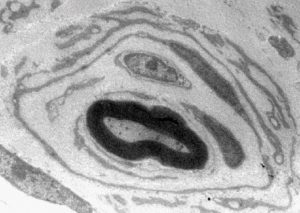

Mehr erfahren zu: "Neue Ansätze zur Heilung verletzter Nerven" Neue Ansätze zur Heilung verletzter Nerven Verletzungen von Nervenfasern an Gehirn, Rückenmark und Sehnerven haben in der Regel funktionelle Verluste zur Folge, weil die Nervenfasern nicht regenerationsfähig sind. Ein Team des Lehrstuhls Zellphysiologie der Ruhr-Universität Bochum […]

Mehr erfahren zu: "Schlüsselproteine für die Reparatur von Nervenleitungen identifiziert" Schlüsselproteine für die Reparatur von Nervenleitungen identifiziert Wissenschaftler des DZNE haben eine Gruppe von Proteinen identifiziert, die beschädigte Nervenzellen nachwachsen lassen.